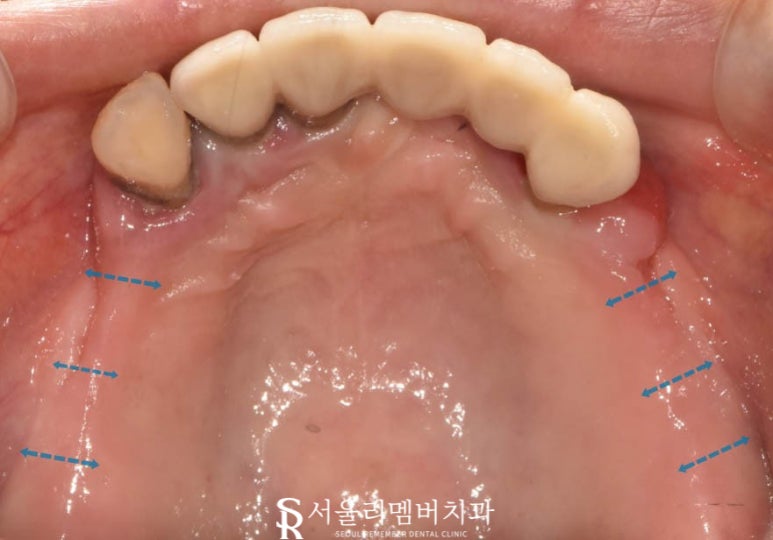

서울대입구역 치과 에서 실제 구강 내를 확인해 본 결과..

치아 상실은 물론이며 여기저기 염증과 치석, 치은 퇴축 등 관리가 잘되지 않았다는 걸 알 수 있었습니다.

어금니 쪽 구치부들은 2개의 약간의 잔존조직을 제외한 채 형태를 찾아볼 수 없었는데요.

그나마 남아있던 앞쪽 전치부도 상황은 같았습니다.

오래된 보철 안으로 충치, 염증, 치주 질환 등이 생겨 주위 잇몸에 물집이 잡히고 부종이 나타나있네요.

보아하니 환자께서 느끼셨을 통증 또한 컸을 것으로 짐작되었습니다.

편하게 식사하는 건 꿈도 못 꾸셨을듯한 구강이네요.

어쩌면 앞쪽 치아들은 살릴 수 있지 않을까? 하며 자세히 살펴보았는데요.

아이고.. 이미 잇몸이 내려앉아 뿌리 부근에 염증이 진행되고 있었습니다.

곧 덜렁덜렁 흔들리고 자연스레 빠져버리게 되겠군요.

아무래도 전체적인 치료가 필요할 것 같습니다.